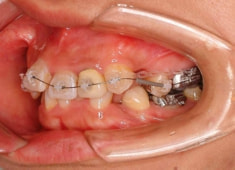

治療後(3年2ヶ月後)